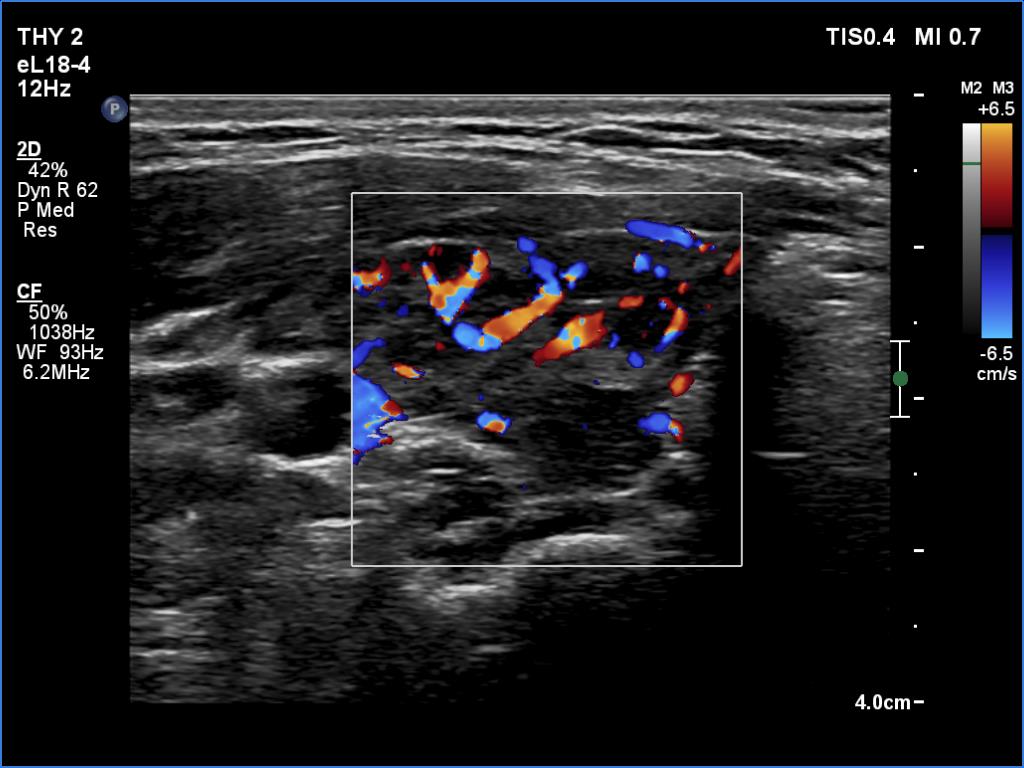

Lymphocytic thyroiditis - case 651 (ultrasonographic picture 3)

Right lobe, transverse view, color Doppler mode. The vascularity is a bit increased.